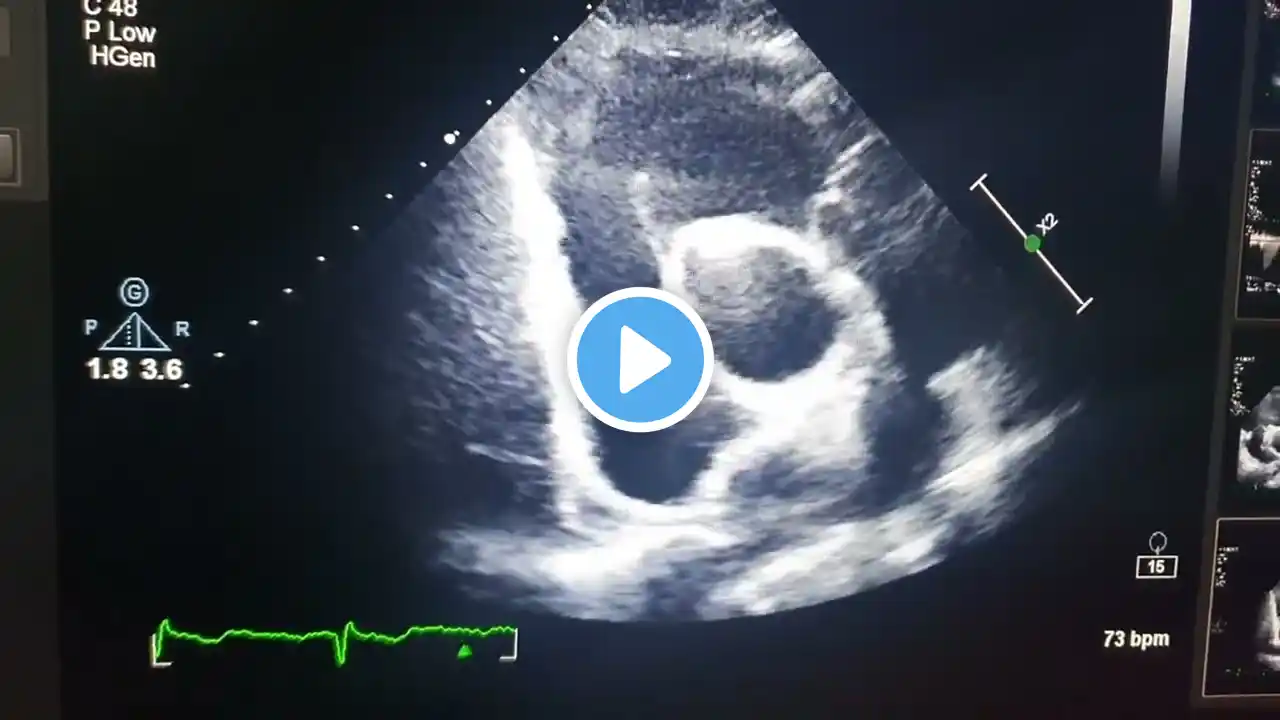

An atrial septal defect is a hole in the wall between two upper chambers of the heart. To close this congenital hole, the doctor will place a special device in the child's heart by catheterization. The total recovery time is 1-2 months. Patient should take rest and walk at a normal pace. After 2 weeks, you can start light exercise. Don't play contact sports for 1 month after surgery. Sexual activity can be resumed 3 weeks after repair. Driving is allowed after 4 weeks. If you need to travel by airplane, walk in the airplane once every hour. Patients can resume work duties after about 6-8 weeks." For treatment assistance in your country or abroad: Email: [email protected] Phone/WhatsApp/Viber: +91-9650001746 Website: www.vaidam.com Vaidam is an ISO and NABH accredited medical assistance company. Patients from 100+ countries have used our services. Useful Links: India Doctors: https://www.vaidam.com/doctors/cardio... Hospitals: https://www.vaidam.com/hospitals/card... Cost of Atrial Septal Defect Closure: https://www.vaidam.com/cost/asd-atria... Turkey Doctors: https://www.vaidam.com/doctors/cardio... Hospitals: https://www.vaidam.com/hospitals/card...